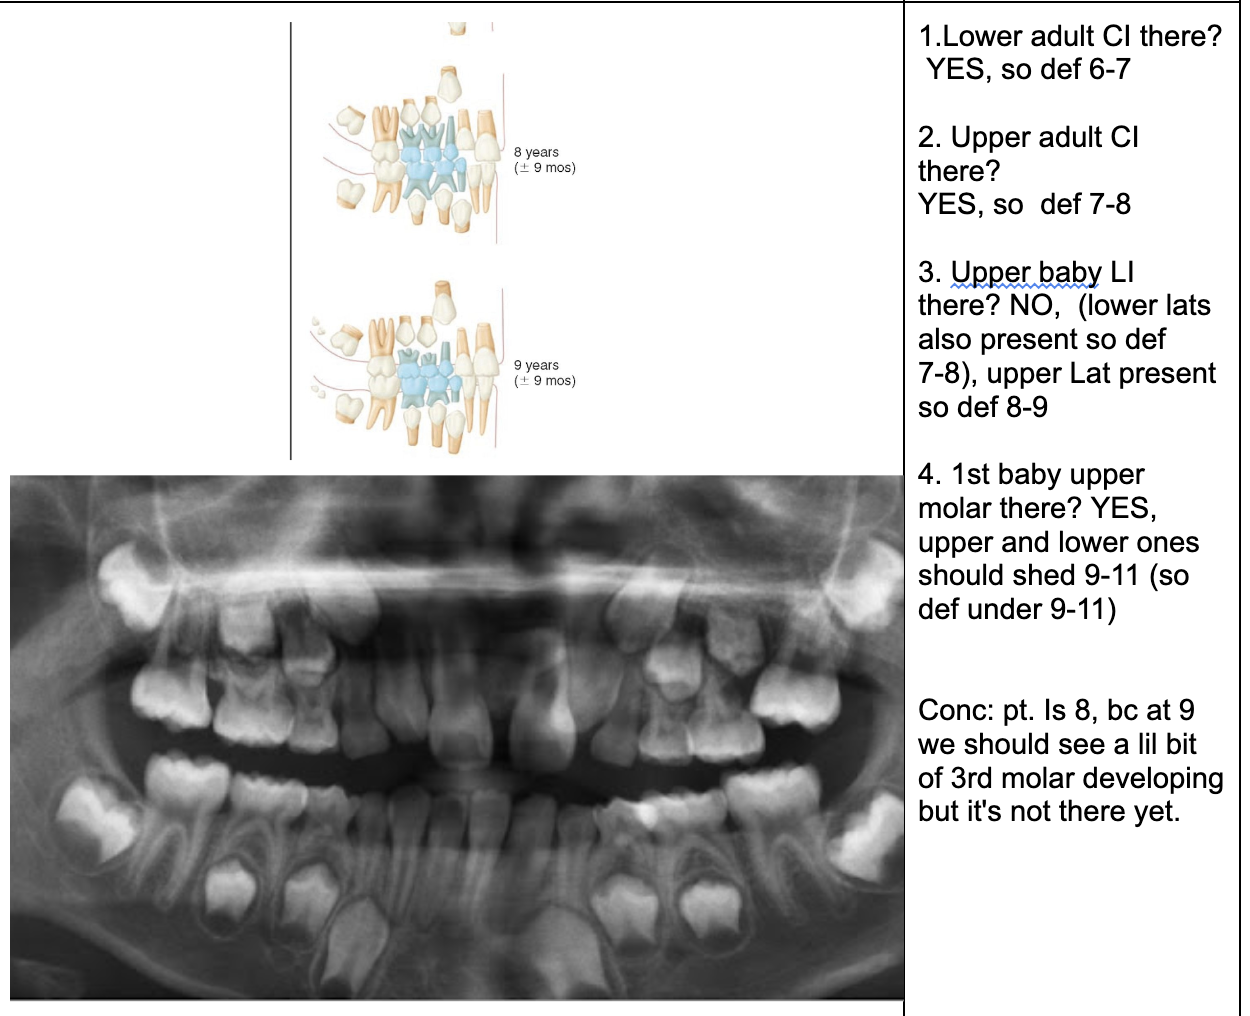

1.Ad. LOWER central incisors present? Yes. definitely 6-7 or older

1. Ad. UPPER CI present? Yes def. 7-8 y.o

3.Ad. Upper LAT incisor present (baby sheds 7-8)? NO so still under 7-8

Conc: pt is under 7